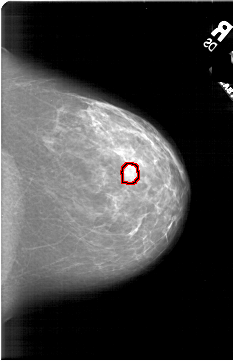

A_1813_1.RIGHT_MLO

RIGHT_MLO LINES 6736 PIXELS_PER_LINE 3976 BITS_PER_PIXEL 12 RESOLUTION 43.5 OVERLAY

FILE: A_1813_1.RIGHT_MLO.OVERLAY

TOTAL_ABNORMALITIES 1

ABNORMALITY 1

LESION_TYPE MASS SHAPE LOBULATED MARGINS ILL_DEFINED

ASSESSMENT 4

SUBTLETY 3

PATHOLOGY BENIGN

TOTAL_OUTLINES 1

BOUNDARY